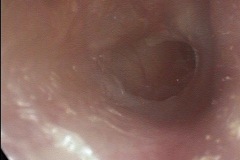

Perforation